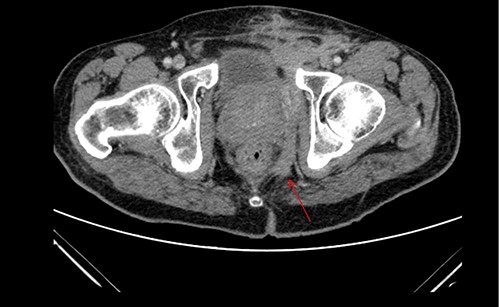

A 61-year-old diabetic patient was admitted from emergency department with septic signs; fever of 39°C, white blood cell count of 20.000/μl, C-reactive protein levels of 156 mg/l and blood glucose levels of 280 mg/dl. For the past 10 days, the patient has noted malodorous anorectal pus discharge, as well as anorectal and suprapubic pain. During macroscopic examination of the perineum, a left-sided abscess in the ischiorectal fossa was identified, with an opening lateral to the sphincteric anal system draining pus. Subsequent digital rectal examination of the anorectal canal could not be completed due to pain, but the initial effort revealed large amounts of pus discharged from anorectal canal. CT and MRI demonstrated an abscess situated in the left ischiorectal fossa and a large supralevator abscess extending cephalad in the extraperitoneal space with a long fistulous tract containing liquid (pus) and gas bubbles, up to the suprapubic area, where erythema with an undulating pus collection below the skin was noted; laterally the pus collection extended up to the left ilio-femoral vessel canal. CT (Fig. 1) and MRI (Fig. 2) were conclusive for the above entity, aptly demonstrating the presence of the two abscess cavities. Proctoscopy under general anesthesia revealed a protruding extra-rectal mass in the left lateral and inferior segment of the rectal ampulla. Finger pressure at this point was accompanied with pus exit from the posterior dentate line of the anal canal at 6 o’clock, through an opening of 1–2 mm in size. Surgery was addressed in three main locations of the pus collection with goal to drain completely the pus; the abscess of the left ischiorectal fossa was drained with enlargement of the external opening of fistula; after curettage, debridement and washing of abscess cavity, a probe was used to detect the internal opening exactly at the posterior dentate line at 6 o’clock. The fistula was characterized as full trans-sphincteric with an extra-sphincteric component in the ischiorectal fossa leading up to the skin. A non-cutting vessel loop drainage seton was then placed. The supralevator abscess was then easily drained from the opening in the posterior dentate line by finger pressure in the left rectal ampulla. A probe following the route of the internal opening upwards to supralevator space led to pus evacuation, allowing this space to be thoroughly washed with water saline solution, using a syringe with a vein catheter. Finally, the suprapubic area was drained with a small stab incision, followed by washing with normal saline. There was a prompt recovery postoperatively, tight control of blood glucose levels, whereas a CT performed 7 days postoperatively (Fig. 3), demonstrated an empty supralevator space with a fistulous tract still present, albeit with significant regression of inflammatory changes.

CT of the lower pelvis; supralevator abscess, with extension upward in touch with the left ilio-femoral vessels. The abscess cavity is shown approaching the skin with a long fistulous tract containing liquid (pus) and gas bubbles (green arrow).